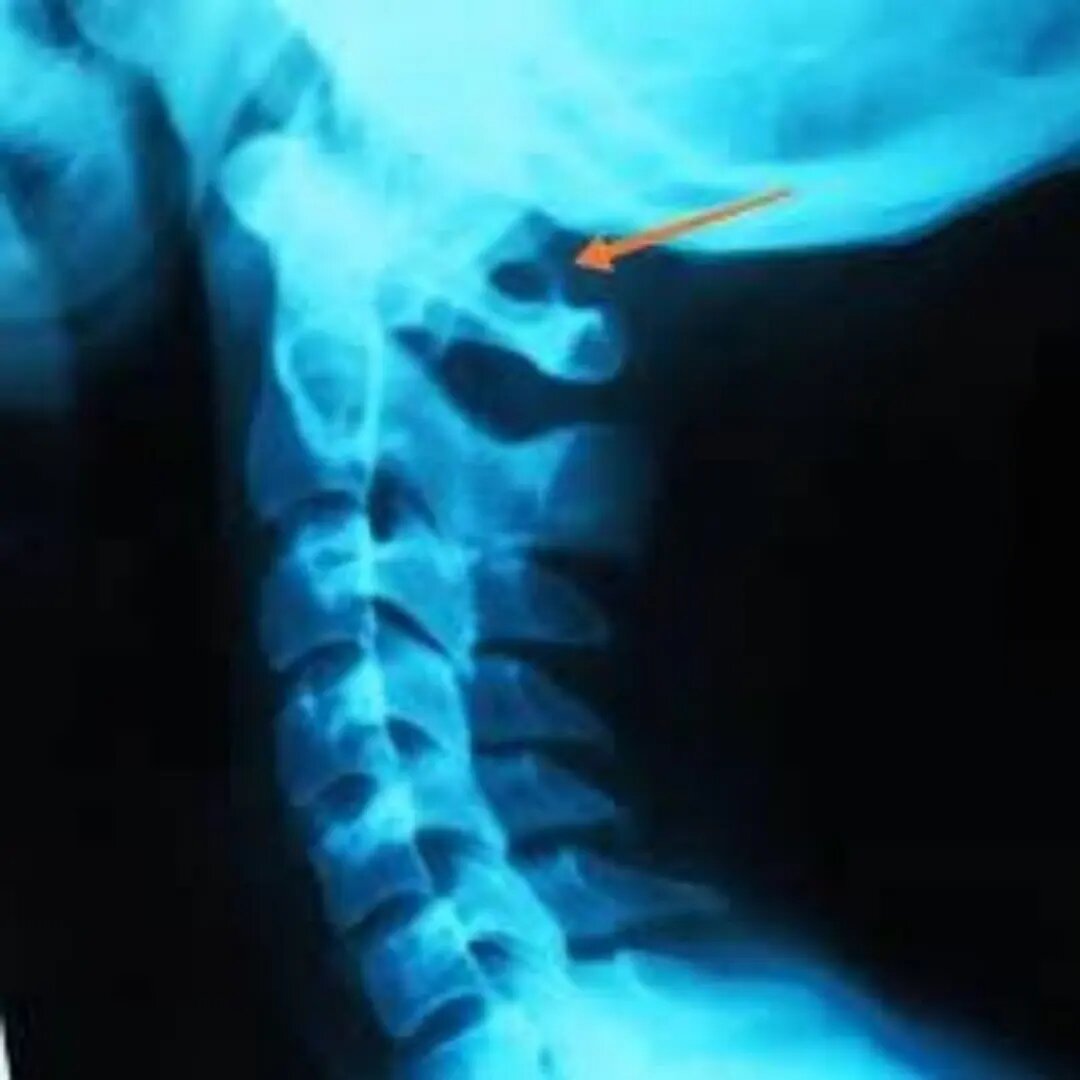

Аномалия Киммерли.

Аномалия Киммерли – врожденная патология строения зоны сочленения черепа с первым шейным позвонком, когда в структуре позвонка, в области его задней дуги, присутствует аномальное костное кольцо (как полное, так и неполное) вокруг одной или обеих позвоночных артерий, ограничивающее движения позвоночной артерии и сдавливающая ее. Это сказывается на кровообращении головного мозга и способствует развитию ишемии в задних его отделах. Частота составляет 10 %. Толщина мостика, который образует кольцо вокруг позвоночной артерии, различна. Он может быть сплошным окостенелым, прерывистым, одно- или двусторонним. О наличии аномалии Киммерли могут говорить такие признаки: 🔺внезапное потемнение и «фейерверки» в глазах; 🔺мигрени, при которых боль обычно концентрируется в затылочной части; 🔺тремор рук; 🔺проблемы с координацией; 🔺частые головокружения и неустойчивая походка, возникающие после резкого поворота головы; 🔺обмороки; 🔺шум и звон в ушах. Подобные симптомы не являются специфическими

Частота составляет 10 %. Толщина мостика, который образует кольцо вокруг позвоночной артерии, различна. Он может быть сплошным окостенелым, прерывистым, одно- или двусторонним.